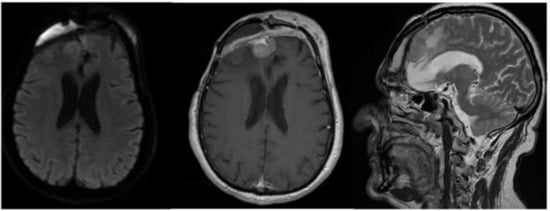

2. Case Report